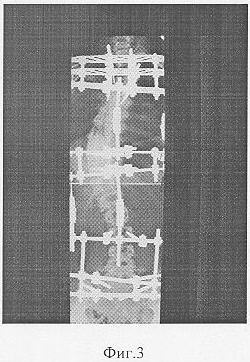

Фиг.3 – копия рентгенограммы в процессе лечения;

В послеоперационном периоде выполняли спондилограммы, на которых измеряли углы деформации и определили темп и длительность дальнейшей дозированной коррекции. При этом контрольные спондилографии выполняли по мере необходимости.